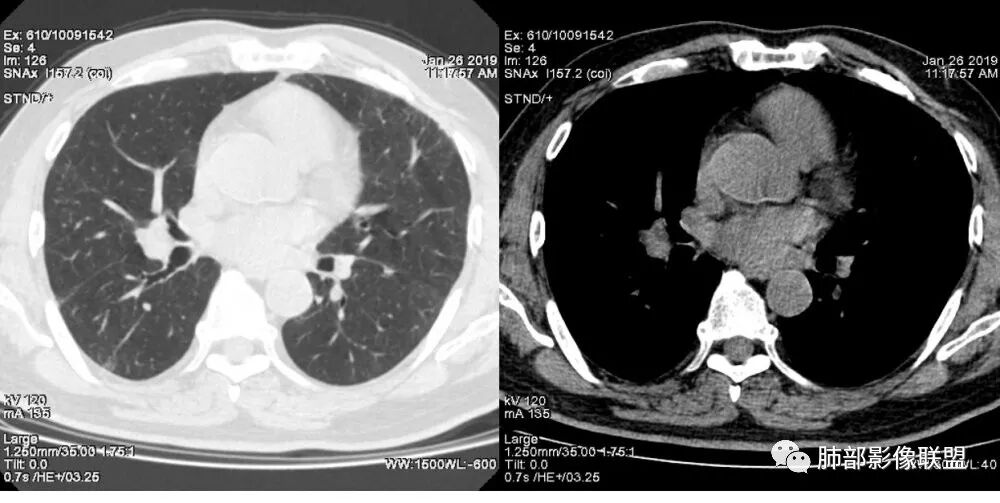

老年女性,右肺下叶沿胸膜下大片状高密度影,外周磨玻璃影,边界较清,内可见蜂窝征及支气管充气征,考虑肺炎型肺癌。

老年女性,咳嗽咳痰病史,右肺下叶大片磨玻璃实变影,胸膜下分布,支气管进入后扩张、僵直,磨玻璃影边界清楚,考虑粘液腺癌。鉴别肺炎。

右肺下叶基底段靠胸膜实变/磨玻璃混杂密度影,边界清楚,内见多发空泡(蜂窝样趋势改变?); 临床:咳嗽咳痰,无发热、胸痛; 考虑腺癌:无发热,感染性病变不首先考虑;部分层面形态类楔形,鉴别肺栓塞

老年女性,右下肺实变影,病灶里有小叶内间质增厚,周围GGo,支气管扩张,粘液性腺癌?淋巴瘤?

中年女性,咳嗽咳痰。右肺下叶片状高密度影,部分实性密度,周围见边界清晰磨玻璃影,内见小空泡,实性区部分支气管堵塞,有重力效应,考虑肺炎型肺癌,建议查痰脱落细胞。

老年人,右肺下叶斑片状阴影,病灶有膨胀性,边缘可见磨玻璃影,其边界清晰,内见僵硬的支气管,部分支气管扩张,首先考虑占位性病变,粘液性腺癌可能。鉴别感染性病变,后者边缘多有收缩性改变或者平直,内部支气管走形自然。

中年女性,右肺下叶沿胸膜下大片状高密度影,实变加GGO,外朝内发展,边界较清,内可见蜂窝征及枯树征,考虑肺炎型肺癌。

右肺病灶,病灶较大,实性+周边ggo,边界清晰,胸膜下分布,长轴平行于胸膜,内部支气管充气征,因不发热,暂不考虑感染性病变,支持肺炎型肺癌。

女性,咳嗽咳痰不发烧,右下外基底段实变影,边缘清楚GGO,有充气支气管征,枯树枝不明显,由外向内;诊断:肺炎型肺腺癌;鉴别:1、肺栓塞(外型神似,但无胸痛丶咯血);2丶肺炎

老年女性,右下肺实变影,糊墙,外朝内发展,病灶里有小叶内间质增厚,周围边界清楚了GGO,支气管扩张明显,考虑粘液癌;不符合点,支气管扩张太厉害了,鉴别淋巴瘤。

患者中年女性,咳嗽咳痰就诊。胸部CT:右肺下叶后基底段片状实变影,由胸膜向内发展呈扇形,病灶里有小叶内间质增厚、蜂窝状影,周围边界清楚GGO,内可见扩张支气管,淋巴结无明显肿大。综合符合粘液腺癌。

老年女性;右下肺混合实变影,呈楔形改变,边缘清晰,支气管进入且扩张,蜂窝状改变,考虑粘膜相关淋巴瘤,鉴别粘液腺癌,肺栓塞。

女,55咳嗽咳痰,右肺下叶片状实变,磨玻璃影及蜂窝影,考虑粘液腺癌。

老年女性,咳嗽、咳痰。右肺下叶沿胸膜下大片状高密度影,外周磨玻璃影,边界较清,小空泡,蜂窝征及支气管充气征,叶间裂串珠征,考虑:肺炎型肺癌,鉴别:肺克,链球菌,NTM等感染。

右肺下叶大片状影,密度不均匀,部分实变部分磨玻璃,大部分病灶尚清晰,其内支气管稍扩张,中年女性,首先考虑粘液腺癌,待鉴别淋巴瘤,常规抗炎治疗后复查。

中年女性,右肺下叶实变,近似扇形,外朝内发展趋势,外围紧贴胸膜面,中心密度略高,边缘密度略低,病灶内支气管略扩张。考虑肺炎型肺癌。常规建议抗炎治疗后复查,如无变化或变化不明显,建议穿刺活检。

胸膜下,实变,毛玻璃影,囊,边界清,枯枝,粘液腺。

老年女性,右肺下叶大片实变,小叶间隔及小叶内间隔增厚,边界较清,其内支气管似乎可见稍扭曲,分支减少。考虑1.肺炎型肺癌2.结合临床除外类脂性肺炎。

起源于胸膜下,实性成分,边缘Ggo,边界清晰,内可见小叶间隔增厚,粘液腺癌可能。建议先消炎后复查。

右肺下叶胸膜下大片状MGGO,其内结构紊乱,可见空泡征,病灶内近端支气管扩张,远端闭塞,形态不规则,边界部分清楚,部分似清非清,考虑粘液腺癌,鉴别淋巴瘤

该病灶主病灶位于胸膜下(肋膈角处),边缘膨隆改变,周围毛玻璃,边界清楚,病灶内支气管僵直,轻度扩张,小分支无,符合枯树枝改变,有多发小空泡(难与支气管区别),应该符合肺炎性肺癌,但无蜂窝,没有增强无法判断有无粘液、血管特点,如果周围显示的空泡是支气管,其已达到远端,这些有符合炎性特点,工作中,我会先抗炎膨后复查再定。

这是潘老师说的外向内吗?右下实变,蜂窝,GGO,支气管变形迂曲,局部膨胀感,肺炎性肺癌,粘液腺癌可能。常规先抗炎再复查。鉴别淋巴瘤,淋巴瘤支气管一般不变形,壁光整,病程长。

1.本例病灶较大片混杂密度影,胸膜下分布为主(未沿着支气管分布),该分布特点可见于大叶性肺炎、干酪性肺炎、淋巴瘤及粘液腺癌等。可惜未提供增强扫描图像。

2.病灶示中央实变区,周围GGO,可见明显小叶间隔增厚,GGO边界清楚,应当考虑到恶性病变的可能性。肺炎因炎性水肿及渗出,影像上边界常模糊不清,注意早期粘液腺癌可出现似清非清的边界。粘液腺癌因粘液成份较多,密度一般偏低,纵隔窗病灶常会消隐或范围会明显缩小,这不同于炎性实变。

3.病灶内支气管走形略显僵直,侧支少(粘液阻塞),也符合肺腺癌的枯树枝征。而大叶性肺炎的支气管是管壁光整、通畅、自然,结核的支气管常常壁增厚,甚至狭窄后扩张;

4.患者临床症状不重,临床炎性指标不高,结合肺内影像,应警惕肺炎型肺癌。